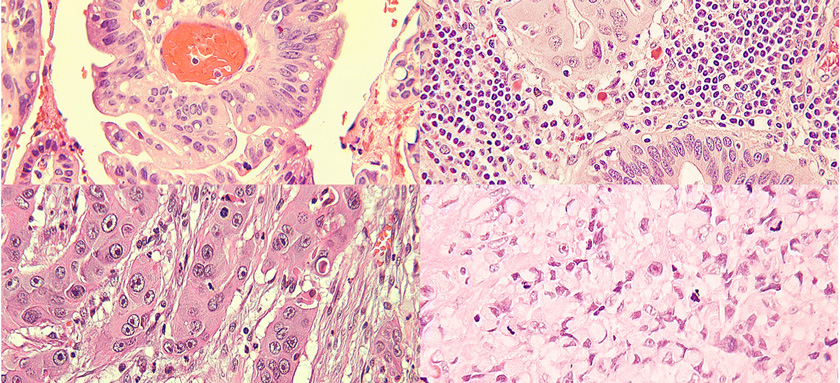

Safra kesesi, kanserine neyin neden olduğu net değil değildir. Doktorlar safra kesesi kanserinin, sağlıklı safra kesesi hücrelerinin DNA'larında değişiklikler (mutasyonlar) geliştirdiklerinde oluştuğunu bilirler. Bu mutasyonlar hücrelerin kontrolden çıkmasına ve normal olarak diğer hücreler ölünce yaşamaya devam etmesine neden olur. Biriken hücreler, safra kesesinin ötesine geçebilen ve vücudun diğer bölgelerine yayılabilen bir tümör oluşturur. Çoğu safra kesesi kanseri, safra kesesinin iç yüzeyini hizalayan glandüler hücrelerde başlar. Bu tip hücrelerde başlayan safra kesesi kanserine adenokarsinom adı verilir. Bu terim, bir mikroskop altında incelendiğinde kanser hücrelerinin ortaya çıkış şekline değinmektedir.